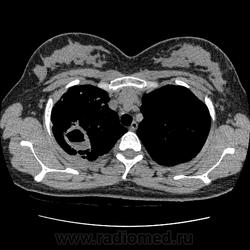

- https://radiomed.ru/sites/default/files/styles/case_slider_image/public/user/19376/img-0001-00042.jpg?itok=2lfc8wWs

- https://radiomed.ru/sites/default/files/styles/case_slider_image/public/user/19376/img-0001-00052.jpg?itok=YRoMhMgw

- https://radiomed.ru/sites/default/files/styles/case_slider_image/public/user/19376/img-0001-00056_0.jpg?itok=nxleffCp

- https://radiomed.ru/sites/default/files/styles/case_slider_image/public/user/19376/img-0001-00061.jpg?itok=rsGqsfJo

- https://radiomed.ru/sites/default/files/styles/case_slider_image/public/user/19376/img-0001-00066.jpg?itok=jCurkizB